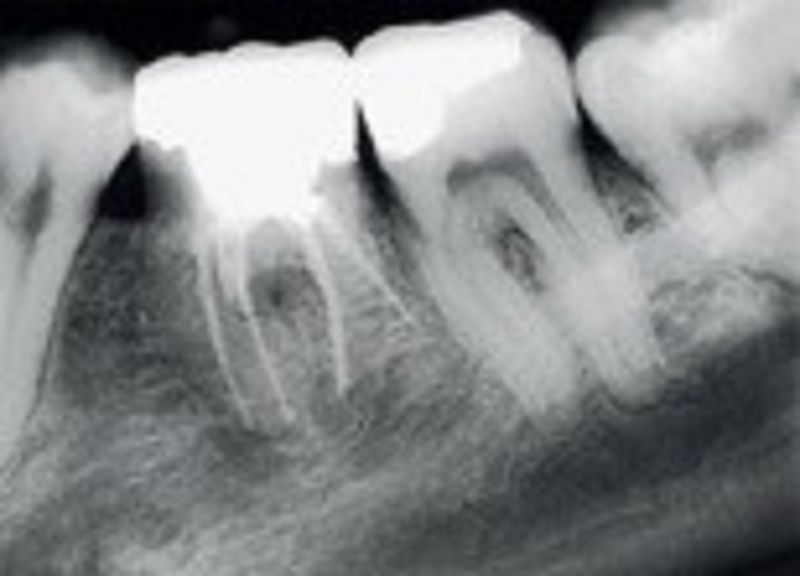

17. The below picture showed?

Unusual root morphology

Hypercementosis of roots

Ankylosed roots

All are correct